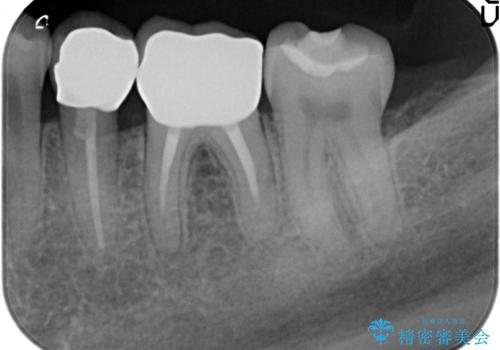

- 「老朽化し古くなった銀歯を白いものにやりかえたい。」と希望され来院されました。

銀歯の下には再発した虫歯やセメントの漏出が見られ、丁寧に除去したのちセラミックによるクラウン・ブリッジ補綴を行います。

適合や精度の悪い銀歯は、時間の経過とともに虫歯の再発リスクが高まります。